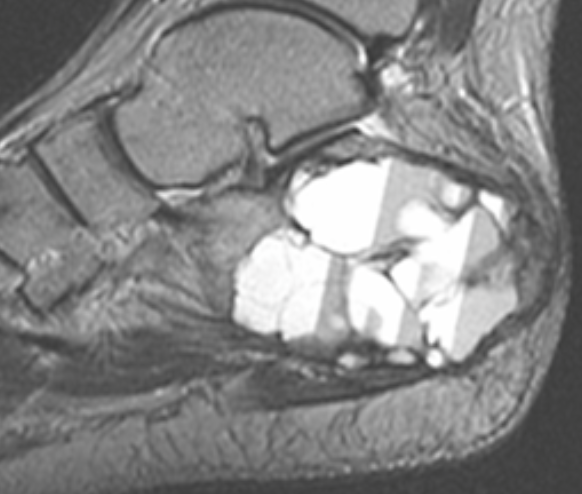

What is seen on imaging of aneurysmal bone cyst

What is the histology of aneurysmal bone cyst?